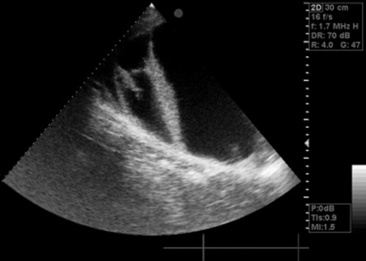

Thoracocentesis

Aspiration from the pleural space is a simple, easily performed, inexpensive procedure that can be both diagnostic and therapeutic. In the horse with septic or neoplastic effusions, sedation is often unnecessary because the procedure causes only minimal additional discomfort. After ultrasonographic evaluation of the thorax, a point is chosen at which drainage or fluid sampling would seem most appropriate—frequently in the sixth or seventh intercostal space 10 cm dorsal to the olecranon and above the lateral thoracic vein. The area should be clipped, if it was not clipped for the thoracic ultrasound examination, and surgically prepared. Multiple sites may be needed in horses with loculated pockets of fluid in the pleural cavity, and these sites should also be chosen using ultrasonography. The skin and intercostal tissue down to the pleura are anesthetized with lidocaine, and a stab incision is made. A sterile 2- to 3-inch teat cannula or bitch catheter is introduced immediately cranial to the rib border to avoid the intercostal nerve and vessel along the caudal aspect of the ribs. The cannula should be attached to sterile intravenous (IV) extension tubing and a three-way stopcock. When the cannula is advanced bluntly through the parietal pleura, a sudden loss of the force required to advance is felt. Aspiration should be attempted at this point. The orientation of the cannula can be varied to reach as much fluid as possible. Normally only a few milliliters of straw-colored fluid are obtained. In cases of pleural effusion, as much as 30 L may be removed from each side of the chest (Fig. 31-3). If fluid is excessive, the tubing can be extended over a bucket for gravity drainage, or a vacuum pump with fluid trap can be attached. Once the procedure is complete, a purse-string suture is placed around the stab incision, and the cannula is withdrawn while the suture is tightened. In cases in which the effusion is large and expected to continue forming for several days, the initial drainage can be performed by placing a chest tube instead of puncturing the pleural space with a teat cannula. If a chest tube is to be left in place it should be secured with a Chinese finger trap suture and the end covered by a Heimlich valve to prevent aspiration of air into the thorax through the tube. If the thorax is being drained rapidly, the patient should be watched carefully for signs of distress, as draining of large volumes can alter cardiovascular parameters significantly.

Fig. 31-3 Thoracocentesis and therapeutic drainage in the horse. Pleural effusion can be large and bilateral. Samples should be obtained for culture and cytologic examination at the time the chest is drained.